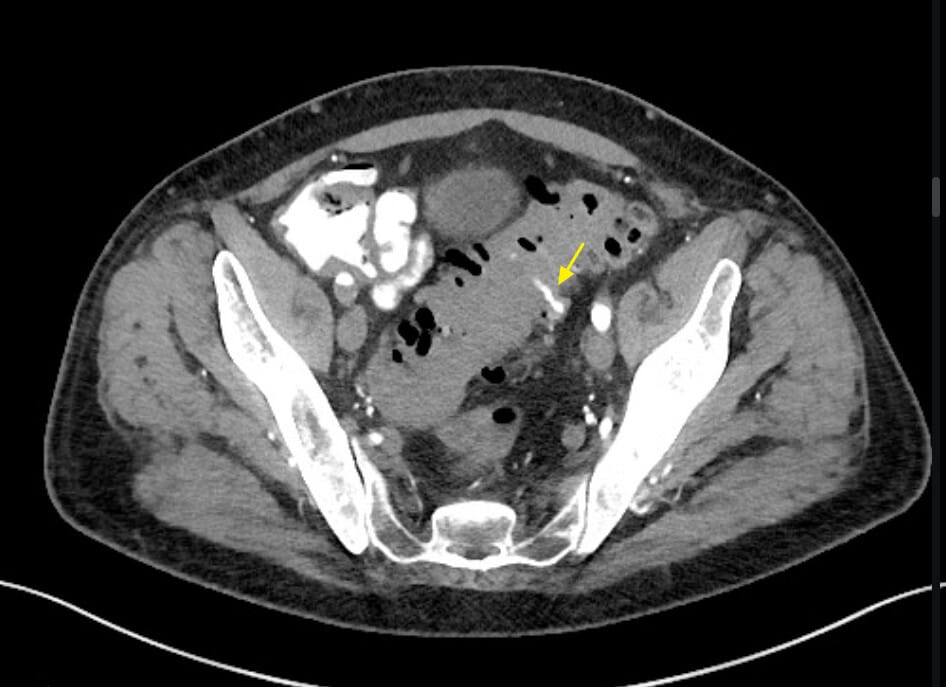

| 🔵 CT 혈관조영(CT Angiography) |

| – 장관 내 조영제 누출(contrast extravasation)이 보이면 활동성 출혈 의미 |

| – 주위에 다발성 게실과 벽의 국소적인 불규칙성 확인 가능 |